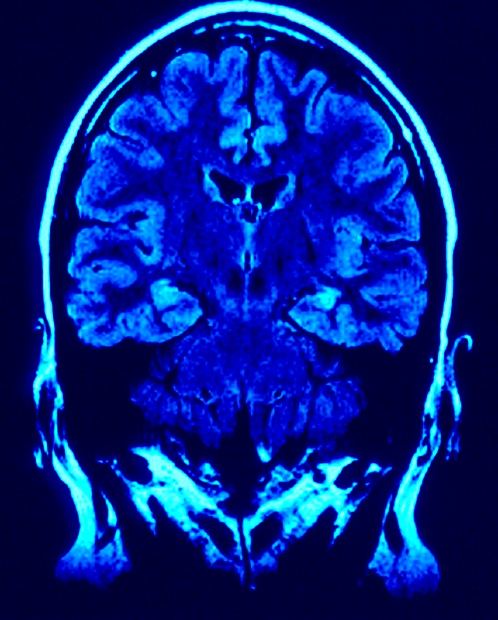

Los procesos neuronales que subyacen en nuestro cerebro son en realidad desconocidos y, aunque son muchos los estudios y experimentos que se están realizando, su complejidad es tal que, de momento, los avances son muy limitados. Estamos tratando de conocer la máquina más compleja y perfecta que existe en el Universo.